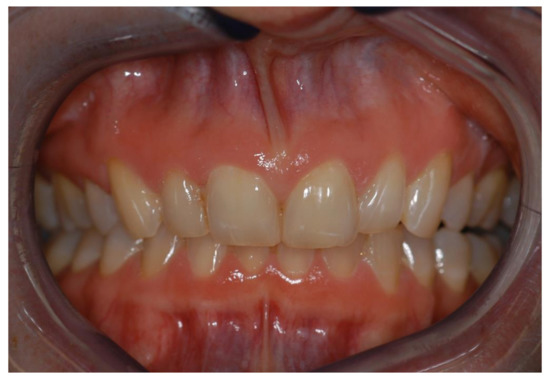

Teeth and gingival tissues are visible during an expressive smile. The observer’s attraction to the perioral region and the emotional signal of the smile has an important impact on attractiveness rating. Asymmetrical crown length and gingival height discrepancies and midline shifts were frequently examined. Most authors came to the conclusion that professionals, especially orthodontists, were more sensitive to asymmetrical changes than laypersons as far as crown length was concerned [23,71,72,73,74,75,76], though difference between laypersons and professionals was not significant in every study group. Anterior midline shifts of the upper central incisor midline in relation to the facial midline had a negative impact on the rated attractiveness at a discrepancy of 1 mm or more to the right and 2 mm or more to the left side, respectively [77]. Figure 6 shows a case with canine coronal height asymmetry and maxillary to mandibular midline shift.

Figure 6.

Anterior teeth of a 64-year-old female patient, exhibiting mandibular midline shift (green line), lower incisor angulation (white dotted lines) and crown height discrepancy between right and left incisors and canines (yellow lines). Treatment included surgical crown lengthening and crowns and fixed partial dentures from left canine to the left molar region. The patient’s main concern was to improve her aesthetic appearance.